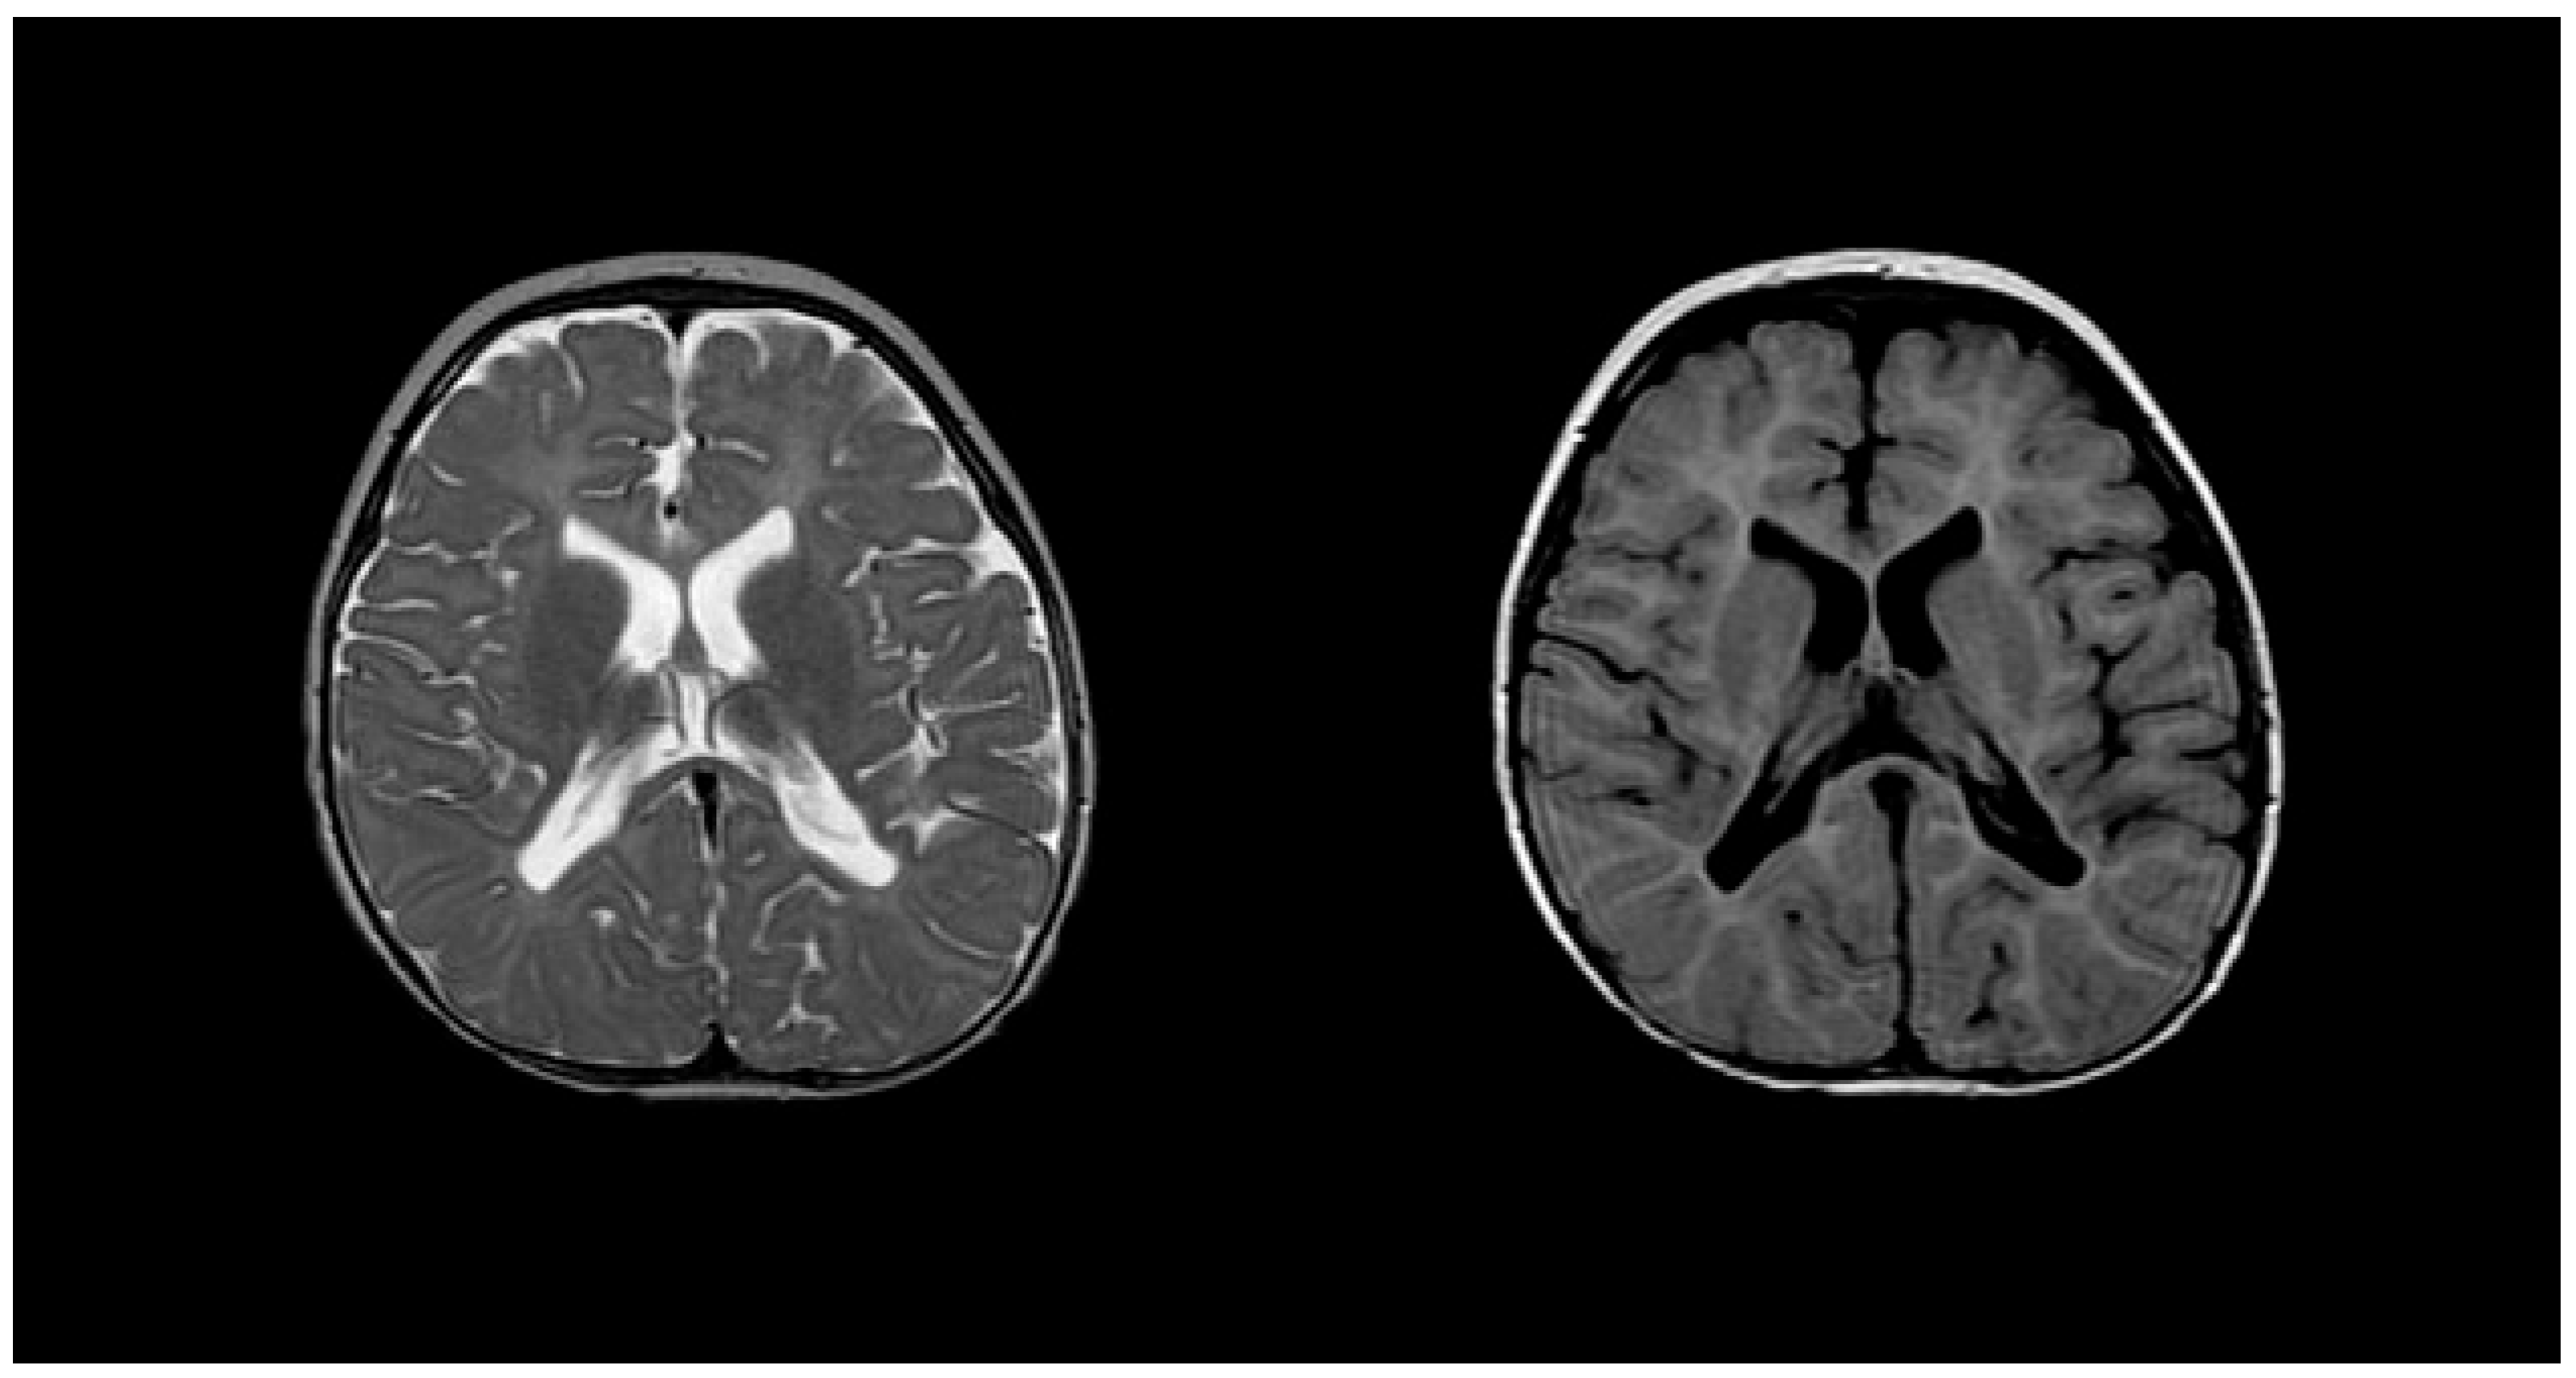

2.7. Aicardi–Goutières Syndrome